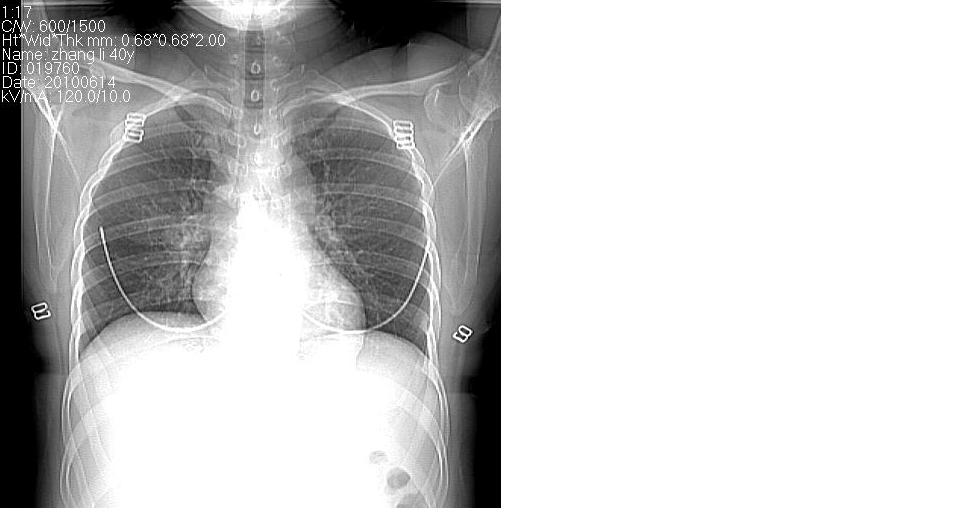

女 40岁,胸片体检发现右肺肿块,无任何症状。

下叶背段多发性小腺泡结节,考虑结核。

肺动静脉瘘可考虑,建议增强